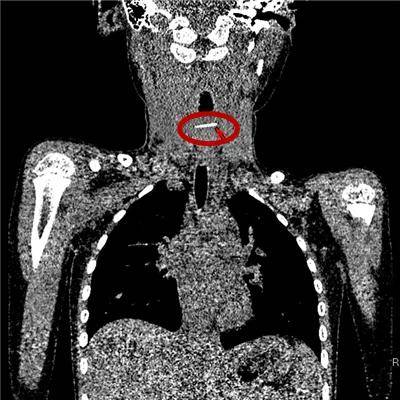

2岁·金属杆

一天前误吞一金属杆状物,约4cm长,患儿偶感腹痛。